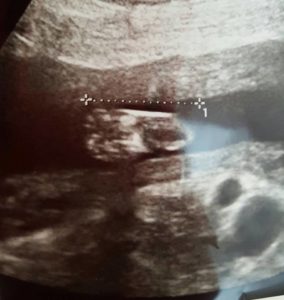

Ich war mal wieder beim Arzt und habe ein bezauberndes Bild vom Fuß unserer kleinen Tochter erhalten ganze 3,2 cm groß – ist das nicht niedlich? Ultraschall ist die beste Erfindung überhaupt und ich freu mich jedes Mal sehr darauf. Nicht so sehr gefreut habe ich mich auf den großen Blutzuckertest, der bei mir aus verschiedenen Gründen vorgezogen wurde – und siehe da? Ich habe eine Diabetesvorstufe wegen grenzwertiger Befunde. Hilfeeee, wer denkt ich sei ohne Kaffee ein ungenießbarer Mensch sollte mich mal auf Diät erleben. Reduktion von Kohlenhydraten und den Blutzucker eine Stunde nach dem Essen im Auge behalten, die Ernährung daraufhin anpassen. Ich bin ja so frustriert 🙁 meine Werte sind zu Hause nämlich leider nicht mehr grenzwertig und ich muss meine gesamte Ernährung umstellen.